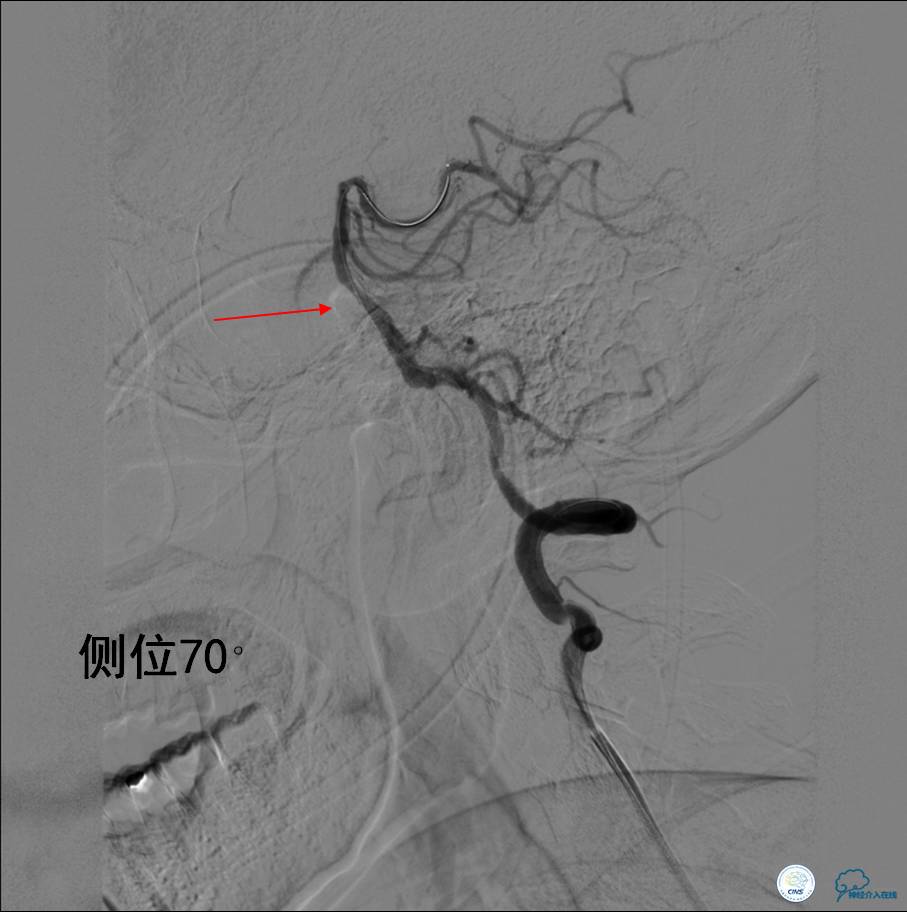

▼支架取栓(Solitaire 6×30)后:血流恢复,仍存在严重狭窄。

Q:支架取栓后仍存在严重狭窄该如何处理?

》根据中国卒中协会2015年指南:机械取栓后,再通血管存在显著的狭窄,建议密切观察,如TICI分级<2b级,建议行血管成形术(球囊扩张或支架置入)(IIb类推荐,B级证据)。

》该患者反复出现原位狭窄和闭塞,经讨论后决定行球囊扩张术+支架置入术。

▼球囊扩张后:狭窄明显改善。